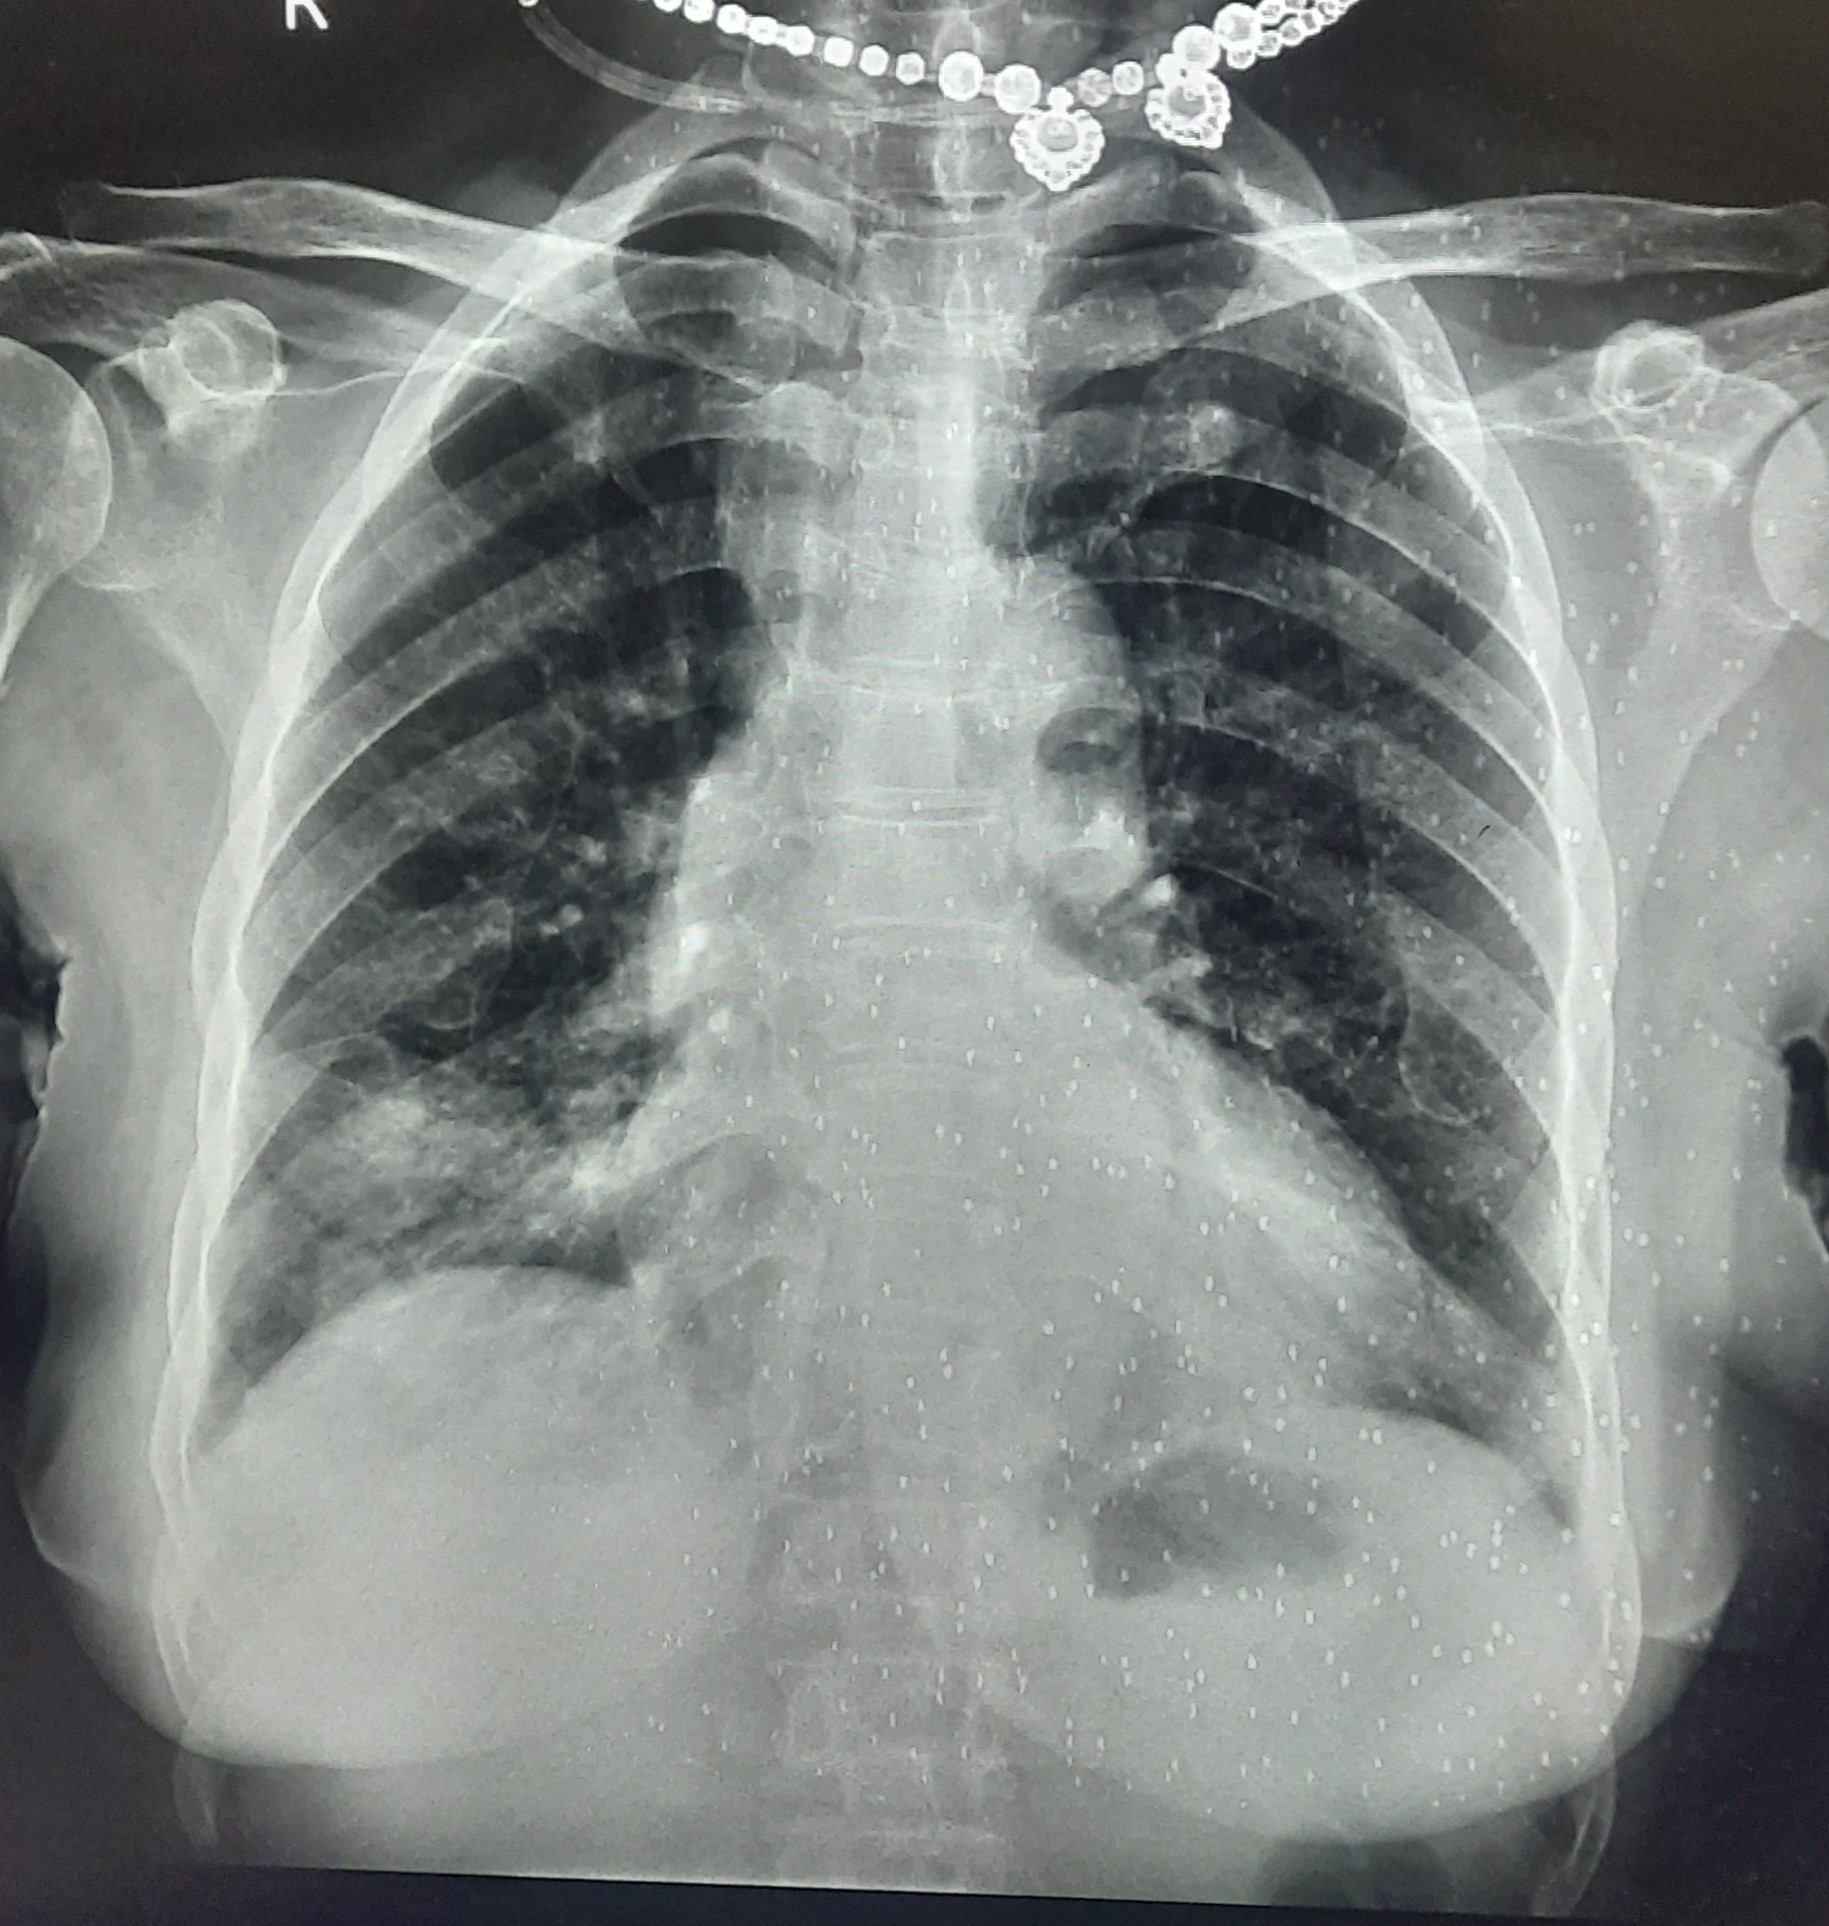

| 209 | IGGMC, Nagpur, Nagpur | P2 | 29-4263 | MONIKA KAITHAL | Consent taken on Paper | 47 Yrs. |

Provisional Diag : B/L LUNG CONSOLIDATION PNEUMONIA?

Final Diag : B/L CONSOLIDATION/PNEUMONIA |

TB Case (Confirmed) | B/L LUNG CONSOLIDATION | Abnormality visible on x-ray |